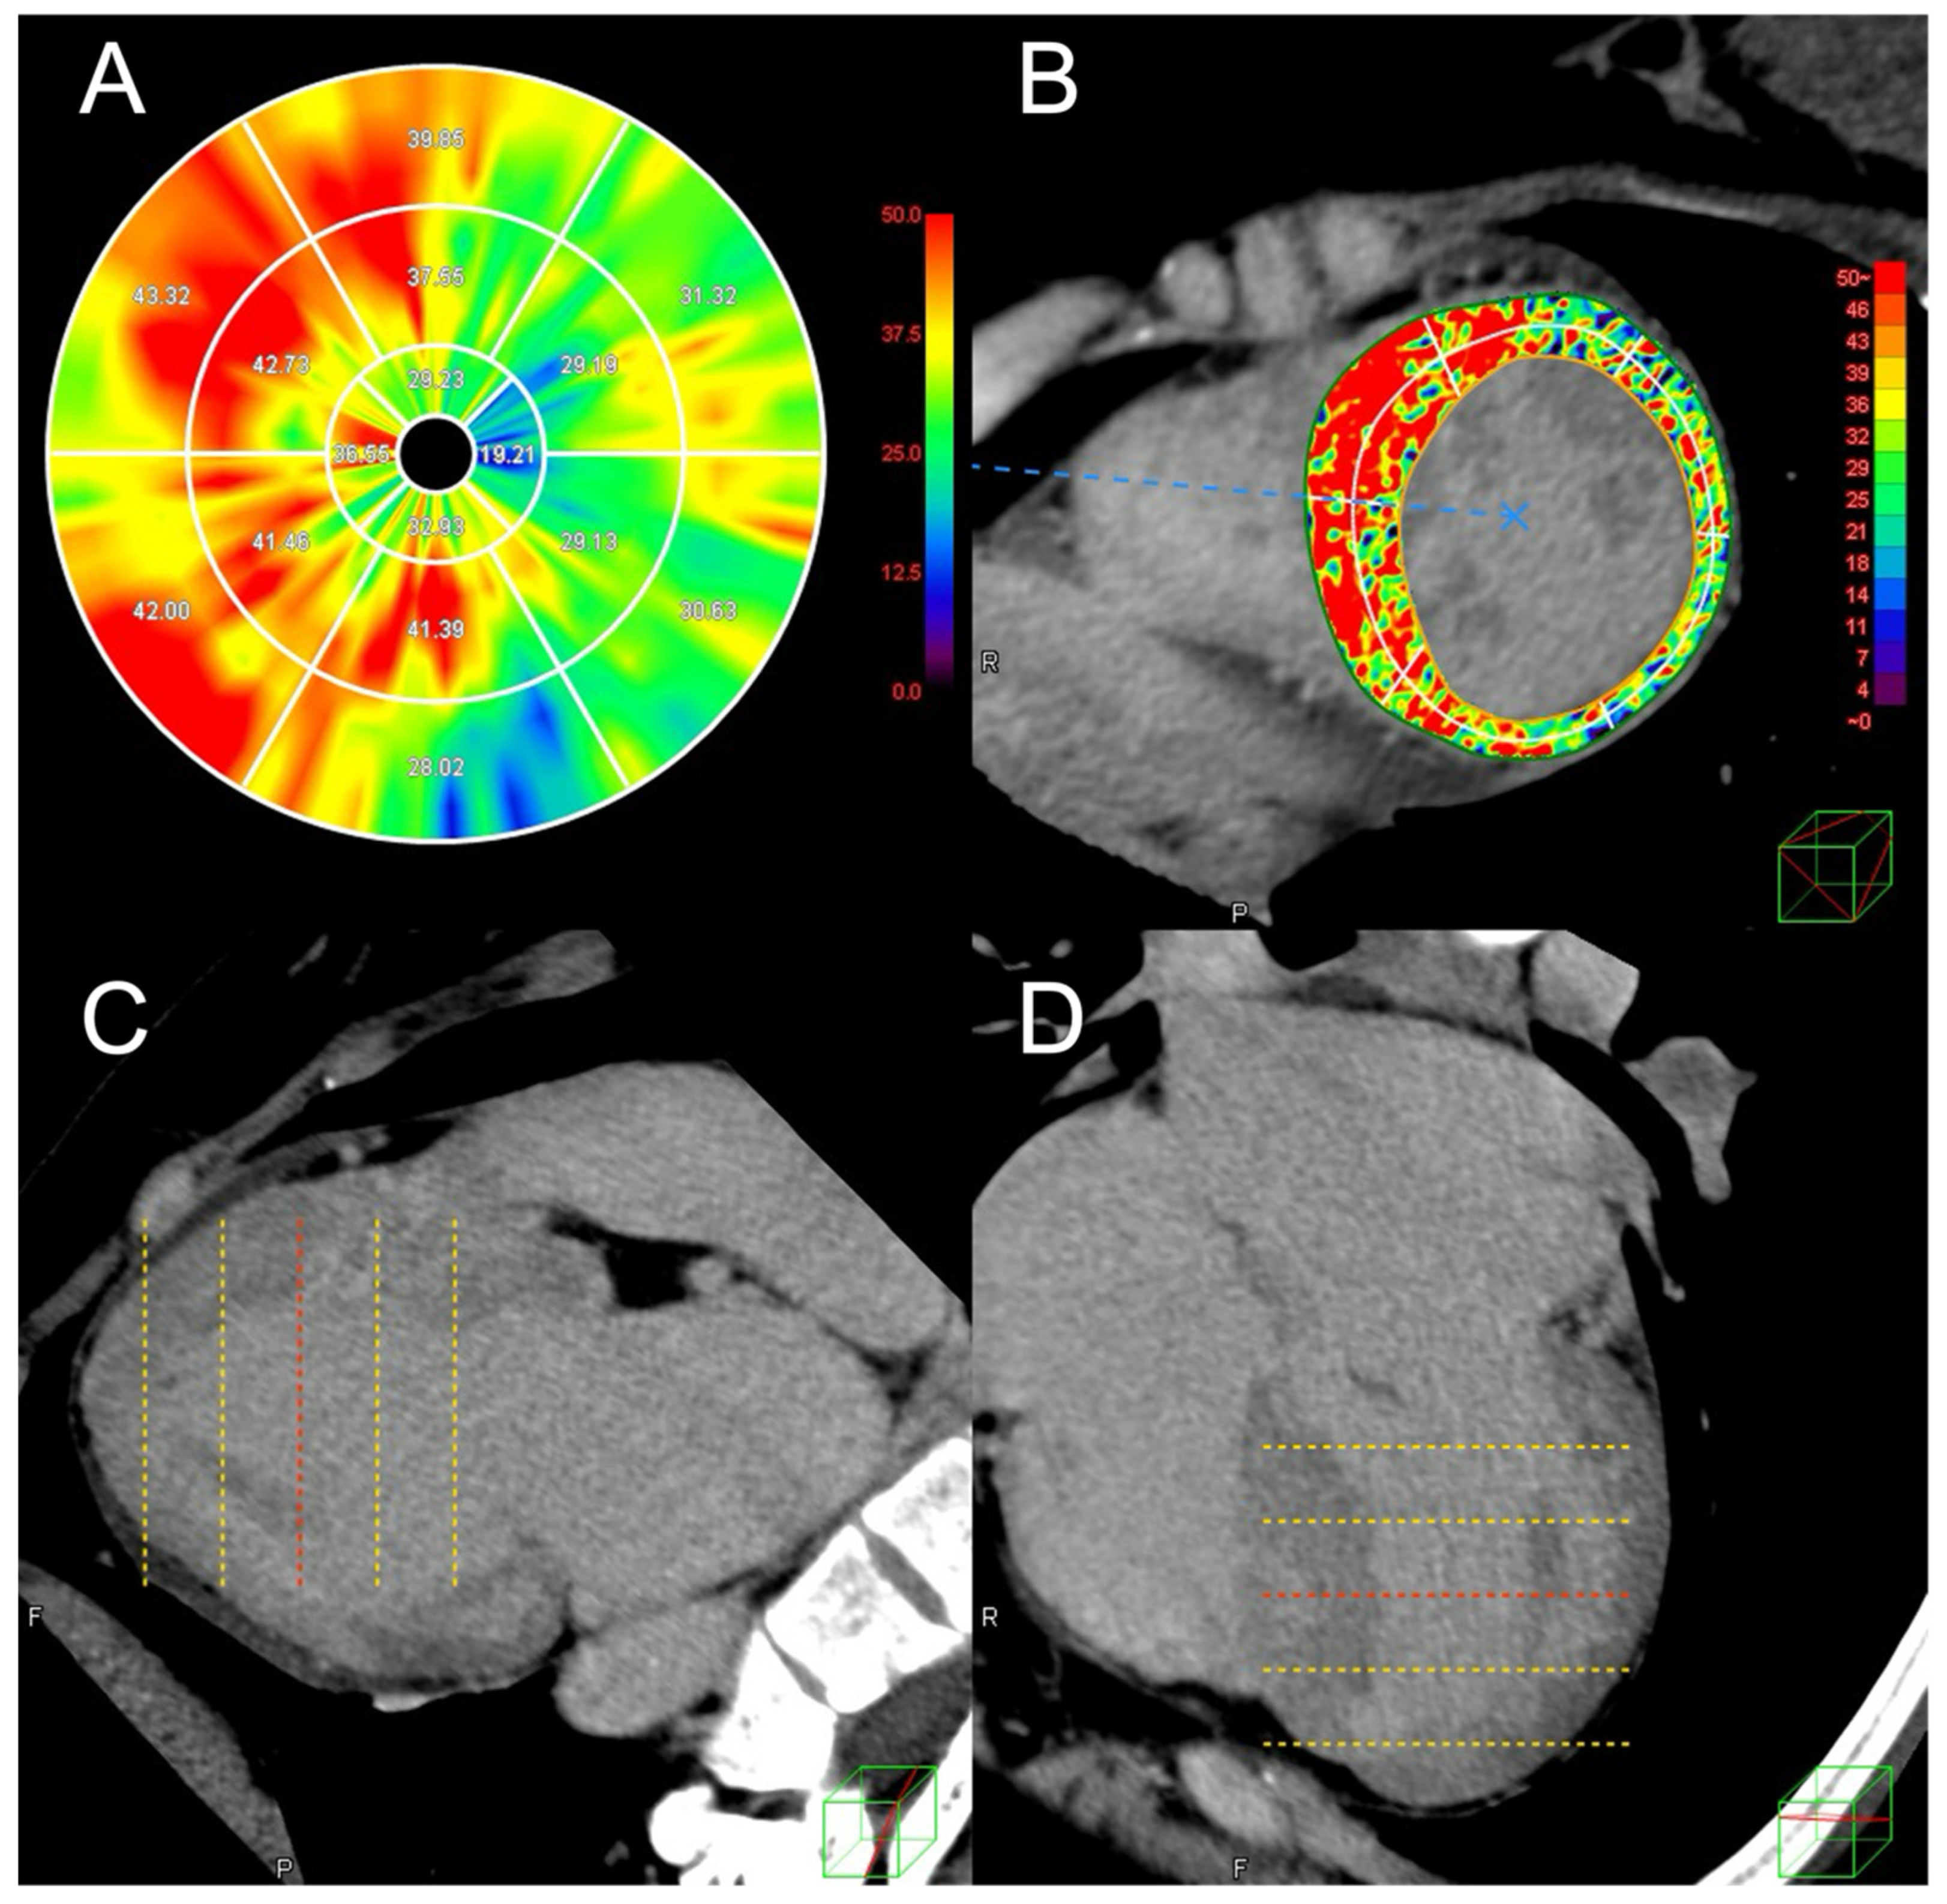

2.2. Analysis of Cardiac CT Images Including ECV